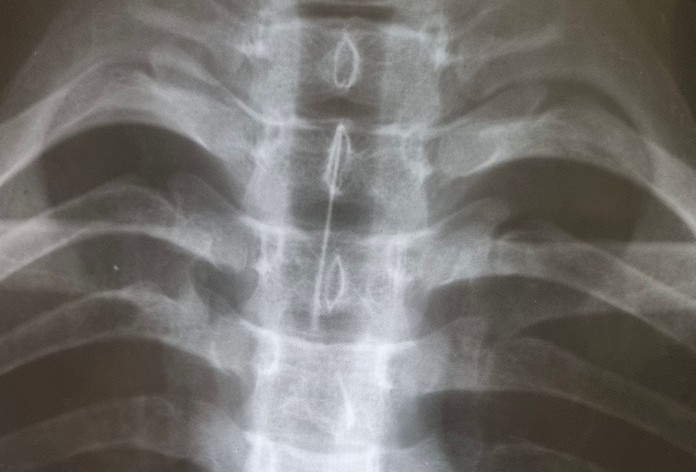

Накануне вечером 15-летний парень смотрел видео на компьютере и при помощи острого предмета решил достать частички пищи, застрявшие в зубах. В какой-то момент он засмеялся и вдохнул иголку. Подростка срочно доставили в больницу города Ангарска, где после рентген-исследования установили местонахождение опасного предмета. Игла с наконечником длиной пять сантиметров застряла в главном бронхе. Для извлечения инородного тела мальчика экстренно привезли в областной центр.

– Игла от шприца находилась в главном правом бронхе острием вверх. Захватить её удалось специальными щипцами «крысиный зуб». При контрольном осмотре признаков повреждения слизистой не обнаружили. Сейчас пациент находится под наблюдением врачей , – рассказала заведующая эндоскопическим отделением, хирург-эндоскопист, кандидат медицинских наук Анастасия Дмитриенко.

Врачи отмечают, что пациенту повезло – острый предмет не повредил бронхо-лёгочную систему, а это при таких случаях большая удача. Лишь у незначительного числа пациентов с неорганическими инородными телами и длительностью их стояния менее суток при повторном обследовании не выявляется патологических изменений в трахеобронхиальном дереве.